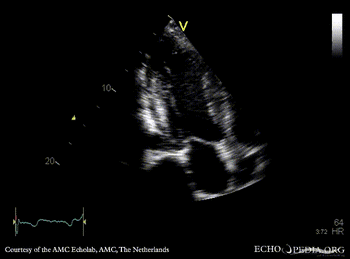

Subvalvular membrane in left ventricle outflow tract

PLAX: subvalvular membrane in left ventricle outflow tract PLAX with Color Doppler: high velocity flow in left ventricle outflow tract